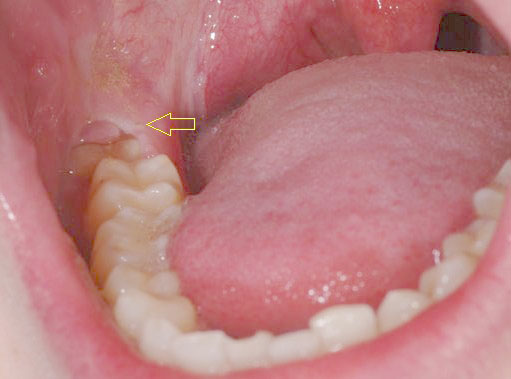

Răng khôn là những răng mọc sau cùng vào tuổi trưởng thành. Khi 28 chiếc thông thường đã mọc đủ trên cung hàm rồi, nếu còn chỗ thì 4 chiếc răng cuối cùng này sẽ được mọc lên ngay thẳng cùng các răng khác. Nếu trên mỗi hàm, các răng đã đủ chỗ thì 2 răng khôn 2 bên sẽ không có chỗ để mọc lên thì nó sẽ bị mọc lệch, mọc ngầm gây nhiều biến chứng.

Các răng mọc lệch,mọc ngầm gây nhồi nhét thức ăn, vùng này lại rất khó vệ sinh làm sạch nên lâu ngày gây nên hiện tượng viêm nhiễm, sưng đỏ, đau quanh thân răng, viêm lợi trùm, cứng hàm, viêm quanh cuống răng. Tình trạng viêm nhiễm kéo dài sẽ phá hủy xương xung quanh răng này và làm xô lệch các răng bên cạnh. Trong các trường hợp nặng có thể gây viêm xương hàm, nhiễm trùng huyết.